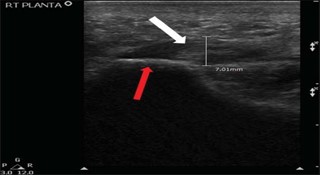

· Plantarfasciitis – inflammation of theplantar fascia, a thick band of tissue that supports the arch of the foot

Among all the causes of heel pain, plantarfasciitis is by far the most common. It occurs when the plantar fascia—athick band of tissue running along the bottom of the foot—becomes inflamed orirritated, often due to overuse, improper footwear, or biomechanicalimbalances.

Morning heel pain is most commonlyassociated with a condition called plantar fasciitis. This occurs whenthe plantar fascia—a thick band of connective tissue running along thebottom of the foot—becomes inflamed due to overuse, strain, or microtears.

After a long period of rest, such asovernight sleep, the plantar fascia tightens. When you take your first stepsin the morning, the sudden stretch of this tightened tissue causes sharppain in the heel. This is often the most intense pain of the day and is akey symptom in diagnosing plantar fasciitis.